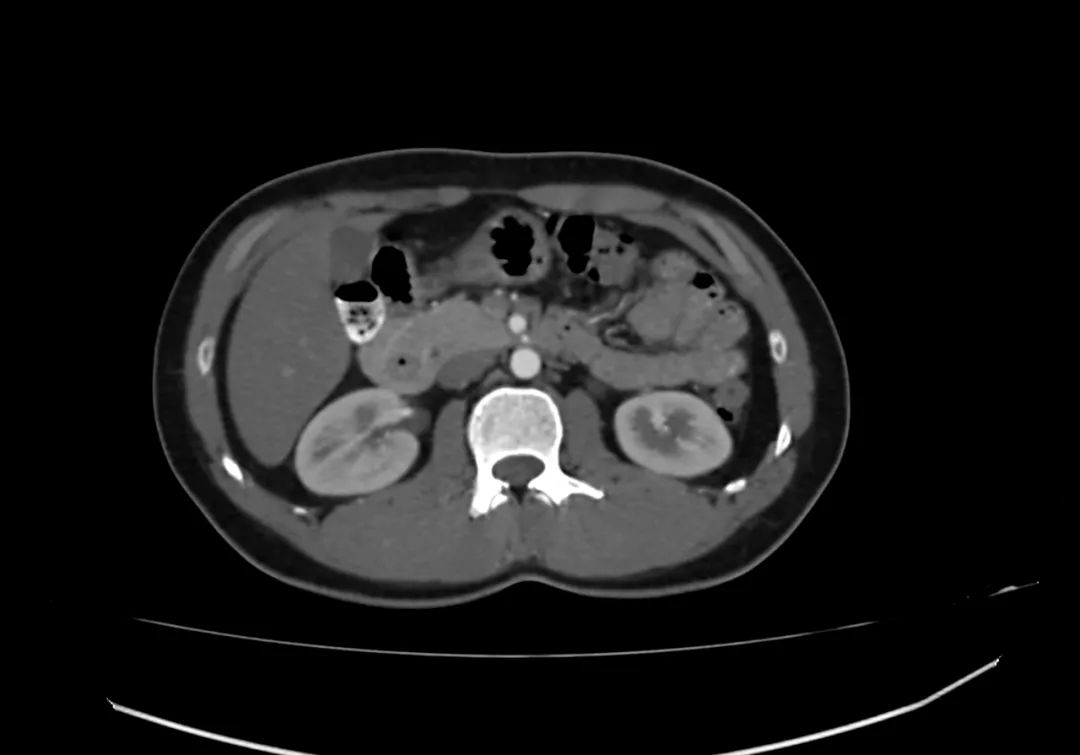

动脉期上腹部轴向增强图像显示胰腺完全包围十二指肠第二部,与完全性环状胰腺一致。

环状胰腺是由腹芽不旋转导致十二指肠被胰腺不同程度包裹的结果。完全性环状胰腺出现在新生儿有梗阻,并可偶然发现在成人,胰腺炎可能是成人的一种表现特征。